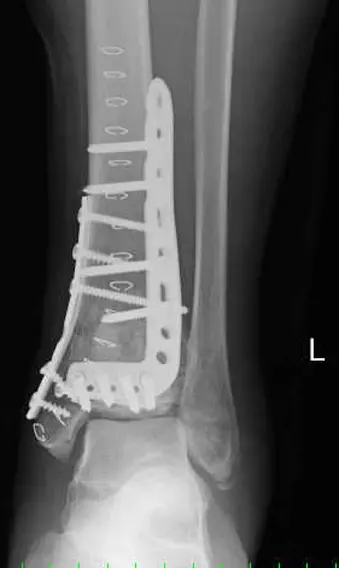

関節内骨折の治療目標は、完全な関節面の再建と骨片間の圧迫により受傷前の状態に機能を戻すことである。そのためORIFを行うが、軟部腫脹が著しく早期にORIFを施行できない場合には創外固定術を施行する。本症例も腫脹が著しく、感染や皮膚壊死の危険があり創外固定術を行った。創外固定術は軟部組織保護のための一時的な処置で、通常1~2週間後に最終的なORIFを行い、本症例も創外固定術後14日目にORIFを施行した。

骨癒合には一次骨癒合(primary bone healing)と二次骨癒合(secondary bone healing)がある。一次骨癒合は骨折部を正確に整復し、圧迫固定を施行した場合に仮骨を形成せずに接触した骨同士がハバース管による生理的骨改変により骨形成が生じて癒合する現象である。二次骨癒合は外骨膜や血腫による軟骨や骨組織の修復で、自己再生self renewal現象の1つである。骨再生能力は若年ほど高く、加齢により低下し、骨芽細胞、骨髄未分化細胞、成長因子などが関与している。骨膜による骨形成を「膜性骨化」、軟骨細胞による骨形成を「内軟骨性骨化」という。骨の血流の多くは骨膜に依存し、骨膜を損傷すると骨形成は不良となる。手術中に骨膜を必要以上に剥離すると骨折部の血流を阻害する。粉砕骨折や開放骨折は骨折部の血流が不良なため二次骨癒合による治療を計画し、LCPは骨折部の角度安定性と血流温存に優れているため頻用される。

骨欠損部分を補う手段として、自分の骨を使う「自家骨移植」、他者の骨を使う「他家骨移植」、人工物で補う「人工骨移植」があり、自家骨移植は生体適合性と吸収置換性が最も高い。本症例も関節軟骨と関節部前方の骨皮質に大きな欠損を認め、自家骨移植術を施行した。

ORIF後20日ほど経過しているが、今後はリハビリを通して関節面の再建、骨移植術の成功を評価していく。